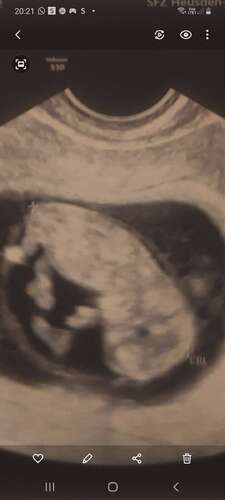

Wat denken jullie 💙🩷

Nog wel mega vroeg.. 10+5, maar ik lijk al een duidelijke nub te zien. Of is het nog echt te vroeg?